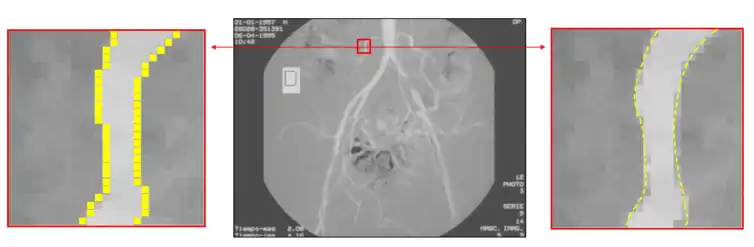

Subpixel

To increase the precision of edge detection, several subpixel techniques had been proposed, including curve-fitting, moment-based,[22][23] reconstructive, and partial area effect methods.[24] These methods have different characteristics. Curve fitting methods are computationally simple but are easily affected by noise. Moment-based methods use an integral-based approach to reduce the effect of noise, but may require more computations in some cases. Reconstructive methods use horizontal gradients or vertical gradients to build a curve and find the peak of the curve as the sub-pixel edge. Partial area effect methods are based on the hypothesis that each pixel value depends on the area at both sides of the edge inside that pixel, producing accurate individual estimation for every edge pixel. Certain variants of the moment-based technique have been shown to be the most accurate for isolated edges.[23]

Edge detection on an angiographic image. On the left, edge detection is made at a pixel level. On the right, subpixel edge detection locates the edge inside the pixel precisely